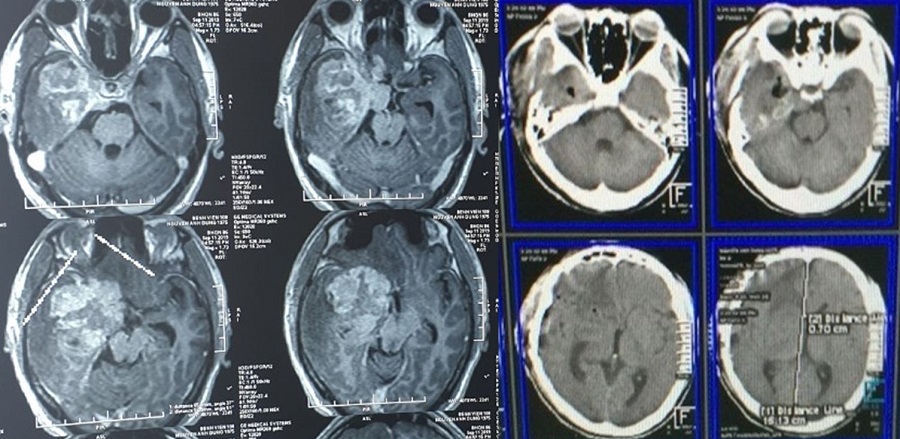

Bệnh nhân N.A.D, 45 tuổi, quê Nghệ An, được chẩn đoán: U não vùng thái dương bên phải, kích thước lớn (5,0 x 5,5 x 6,0 cm). Khối u nằm sâu, xung quanh có nhiều cấu trúc mạch máu, thần kinh quan trọng như động mạch cảnh, vùng nhân xám trung ương... Vấn đề đặt ra là làm sao để lấy tối đa khối u trong khi vẫn bảo tồn được các mạch máu, các cấu trúc thần kinh quan trọng của bệnh nhân.

Hình ảnh phim chụp trước và sau mổ, khối u cơ bản được lấy triệt để